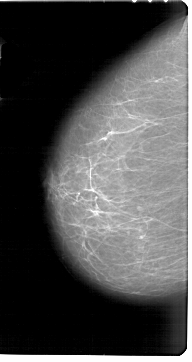

A_1765_1.LEFT_CC

LEFT_CC LINES 6871 PIXELS_PER_LINE 3646 BITS_PER_PIXEL 12 RESOLUTION 43.5 NON_OVERLAY